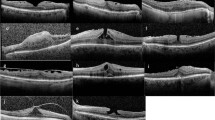

We developed a new parameter to quantitatively assess the irregularity of CSI for SS-OCT images. CSI irregularity index is defined as the weighted sum of differences at each measured point between the CSI on optical coherence tomographic image and its best-fit spherocylinder. Briefly, the horizontal OCT scan image passing through the central fovea was imported into Matlab R 2017b software (MathWorks, Natick, MA, USA). Before importing images into Matlab software, the CSI was manually delineated by two masked observers (M.K. and R.Y.K.). At first, the graders judged the CSI irregularity in an intuitive manner. CSI may be either be bowl-shaped (regular) or follow the natural oval shape of the globe or be inflective (irregular)18. We compared the parameters according to these 2 groups. After importing images into Matlab software, the image was pre-processed to remove background noise, with the thresholding filter in Matlab used to differentiate intensity between background and the signal from the CSI. The contour of the CSI was subsequently extracted and curve-fitted using a third-order polynomial. The Polyfit function was used to fit the coordinates by following the least square principle. The polynomial curve was used for curve fitting with the Curve Fitting Tool in Matlab software. The order of polynomial function was determined to identify the best approximation to the shape of the CSI. In addition, the shape of the CSI was approximated as a smooth curve without any sharp point. The definition and a representative image of measurement of the CSI irregularity index are shown in Fig. 2.

The definition and a representative image of measurement of the CSI irregularity index. (A) The hatched area between the choroidoscleral interface (CSI) on optical coherence tomography and its best-fit spherocylinder demonstrate the concept of the CSI irregularity index, which is defined as the weighted sum of differences at each measured point between the CSI on optical coherence tomographic image and its best-fit spherocylinder. (B) Before importing images into Matlab software, the CSI was manually delineated. (C) After removing background noise with the thresholding filter in Matlab software, the contour of the CSI was subsequently extracted. (D) The polynomial curve was used for curve fitting with the Curve Fitting Tool in Matlab software. The order of polynomial function was determined to identify the best approximation to the shape of the CSI. The Polyfit function was used to fit the coordinates via the least squares principle. CSI irregularity index = 12.6665.